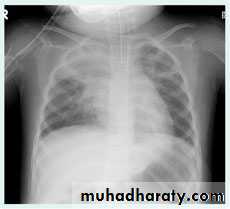

Right upper lobe consolidation

RUL consolidation will be seen as an increased opacity within the right upper lobe. Opacity may be sharply bordered by the horizontal fissureSome loss of outline of the upper right heart border may be apparent

Radiological sign in chest radiograph

Dense opacity seen above the horizontal fissure.

Air-bronchogram line

The lower border of the consolidation is sharply delinated by the horizontal fissure suggesting it lies in the anterior segment of the RUL